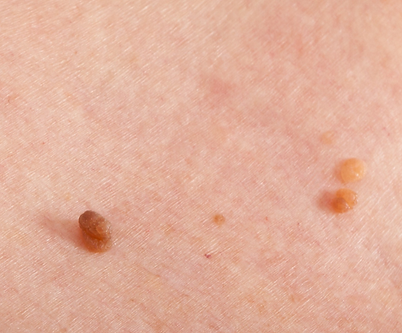

Kožní výrůstky, pigmentové znaménka nebo drobné nerovnosti pleti mohou být nejen estetickým, ale i zdravotním problémem. Na naší klinice je odstraňujeme pomocí moderních laserových technologií, které zajišťují vysokou přesnost, minimální zásah do okolní tkáně a rychlé hojení.

chtějí odstranit nevzhledné nebo mechanicky obtěžující výrůstky (např. v místech tření oblečení nebo šperků)